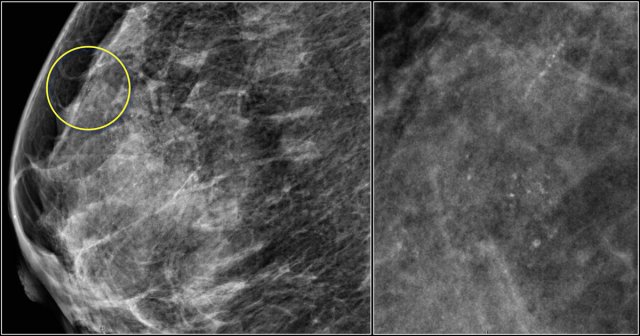

Notice the distortion of the normal breast architecture on oblique view (yellow circle) and magnification view.

A resection was performed and only scar tissue was found in the specimen.